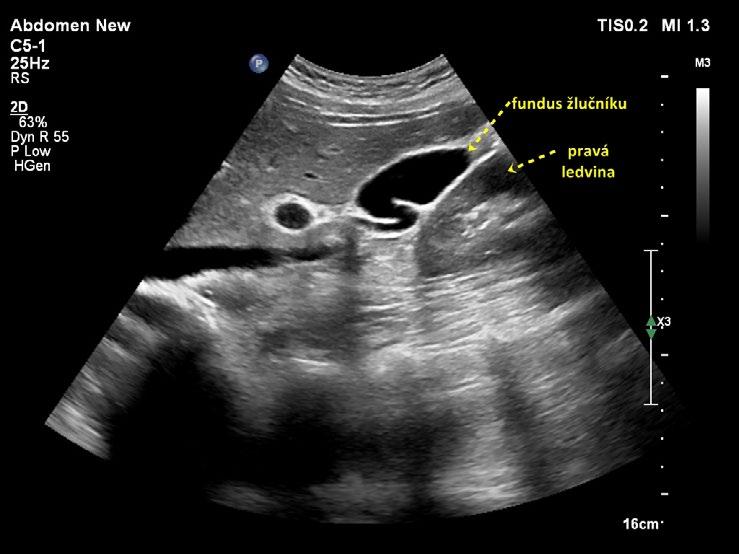

Žlučník prohlížíme v celém rozsahu (krček, infundibulum, tělo a fundus), v dlouhé a krátké ose a ve více rovinách zobrazení. V krčku lze příležitostně zobrazit spirální slizniční řasu (Heisterovu chlopeň). Za spirální řasou vzniká dorzální akustický stín, který může vést k mylné diagnóze konkrementu v krčku žlučníku. Krček a infundibulum žlučníku mají vztah k hilu jater a jsou místy, kde hledáme případný zaklíněný konkrement při akutní cholecystitidě. Fundus je uložen pod spodní plochou jater a přibližuje se k přední břišní stěně nejčastěji v medioklavikulární čáře, jeho uložení je však značně variabilní – od levé subhepatické oblasti až do pravé prerenální pozice (obr. 1.3). Fundus je místem, kde dochází nejčastěji k perforaci žlučníku při akutní komplikované cholecystitidě.

Obr. 1.3 Prerenální uložení fundu žlučníku